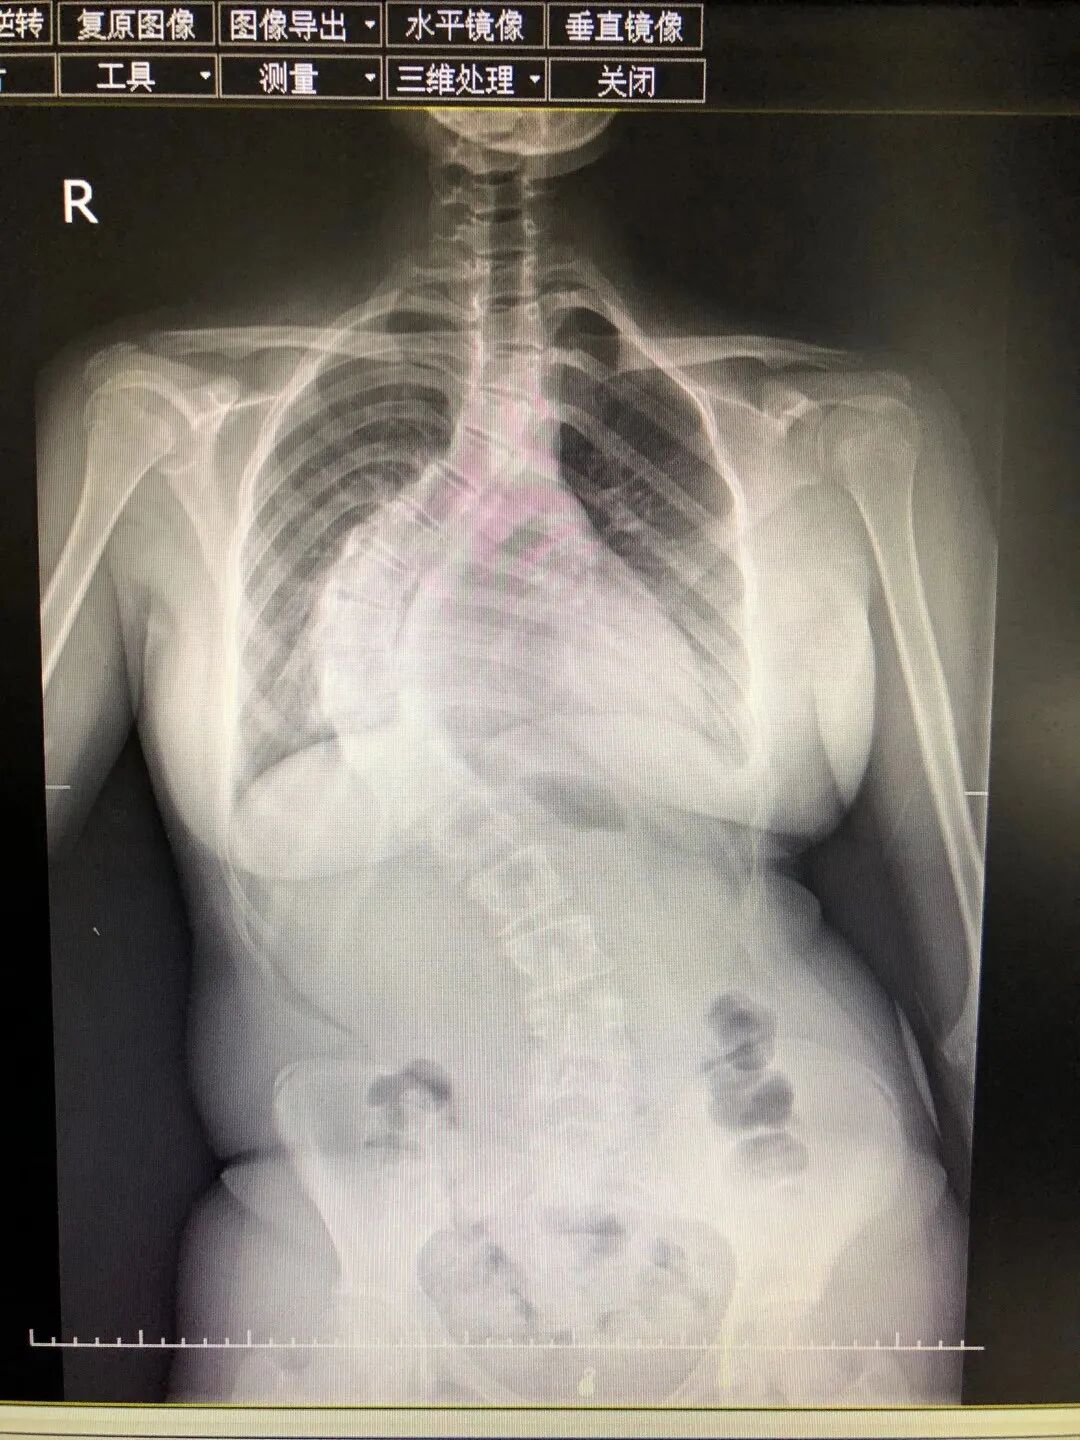

●13岁男孩的“挺胸”新生

初中生小伟(化名)因45°严重脊柱侧弯自卑度日,科室团队借助3D打印技术定制精准方案,完成三维矫形手术。术后他身高增5厘米,体态恢复正常,终于能像同龄人一样自信抬头。